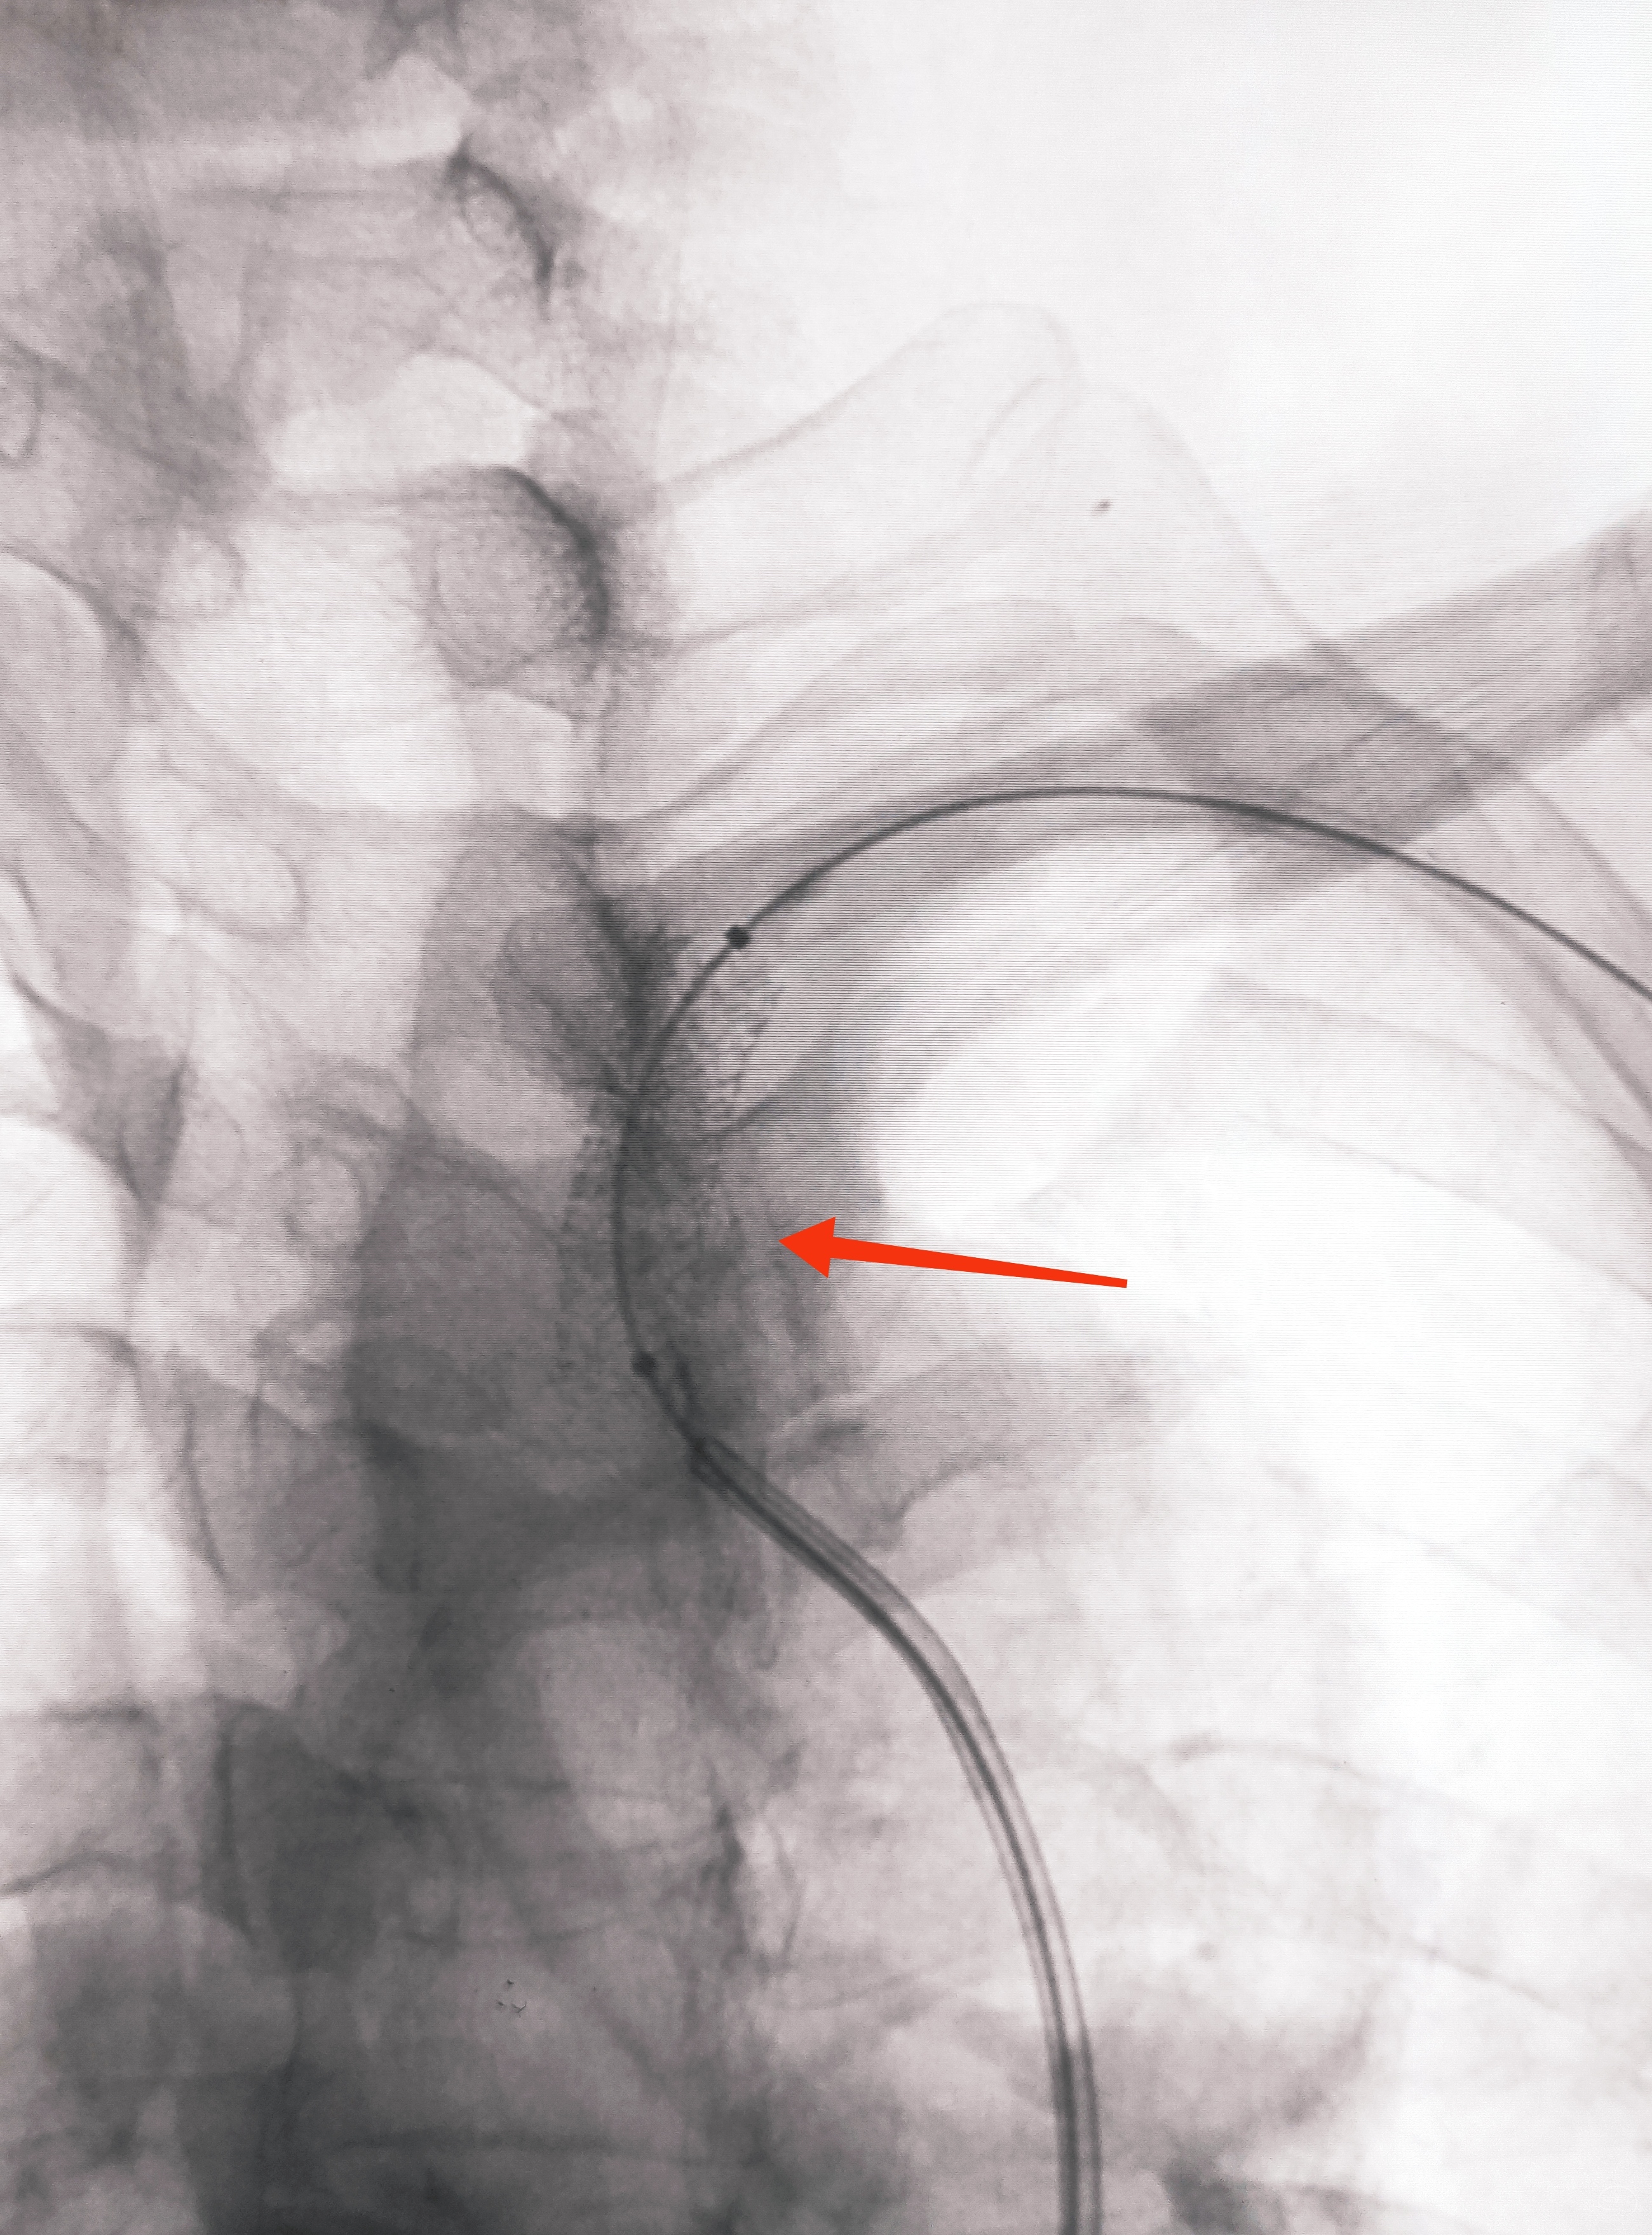

造影显示了依旧闭塞的左侧锁骨下动脉,依旧的逆向盗血

小球囊+大球囊,梯度预扩

一切看似理想,一切看似简单,诡异的事情还是发生了,8F导引导管死活无法进入左侧锁骨下动脉,各种方法尝试个遍:泥鳅走远,单弯挂口,Sim挂口,屡战屡败(水平退步明显,不应该啊,夹层?),因为怕折腾,因为想安全,怕进假腔,弄出夹层。索性换一个思路:空中接力,构建桡-股动脉大环线

6F导引导管造影确认支架置入部位

支架导引导管内先通过,再回撤技术,顺利释放雅培9×29球扩支架